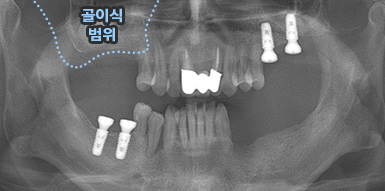

치주염 등으로 치조골(잇몸뼈)의 양이 부족한 경우

치조골 이식술을 통하여 충분한 뼈의 양을 확보한 후

임플란트를 식립합니다.

뼈의 밀도가 치밀하고 단단하며, 양이 충분할수록 임플란트의 성공률이 높아집니다.

청담네오플란트는 풍부한 경험의 의료진이 치조골 이식술을 통해 치조골을 적절한 양과

밀도로 재생시킨 후 임플란트를 식립합니다. 뼈의 흡수가 심하지 않아 적은 양의

치조골 이식을 하는 경우 임플란트 식립을 동시에 진행할 수 있지만, 뼈의 흡수가

심하여 많은 양의 치조골 이식이 필요한 경우 치조골 이식술을 먼저 진행한 후,

치조골이 재생되면 임플란트를 식립하여 보다 정밀하고 안전한 시술 결과를 얻을 수 있습니다.

치조골 이식술 전후사진